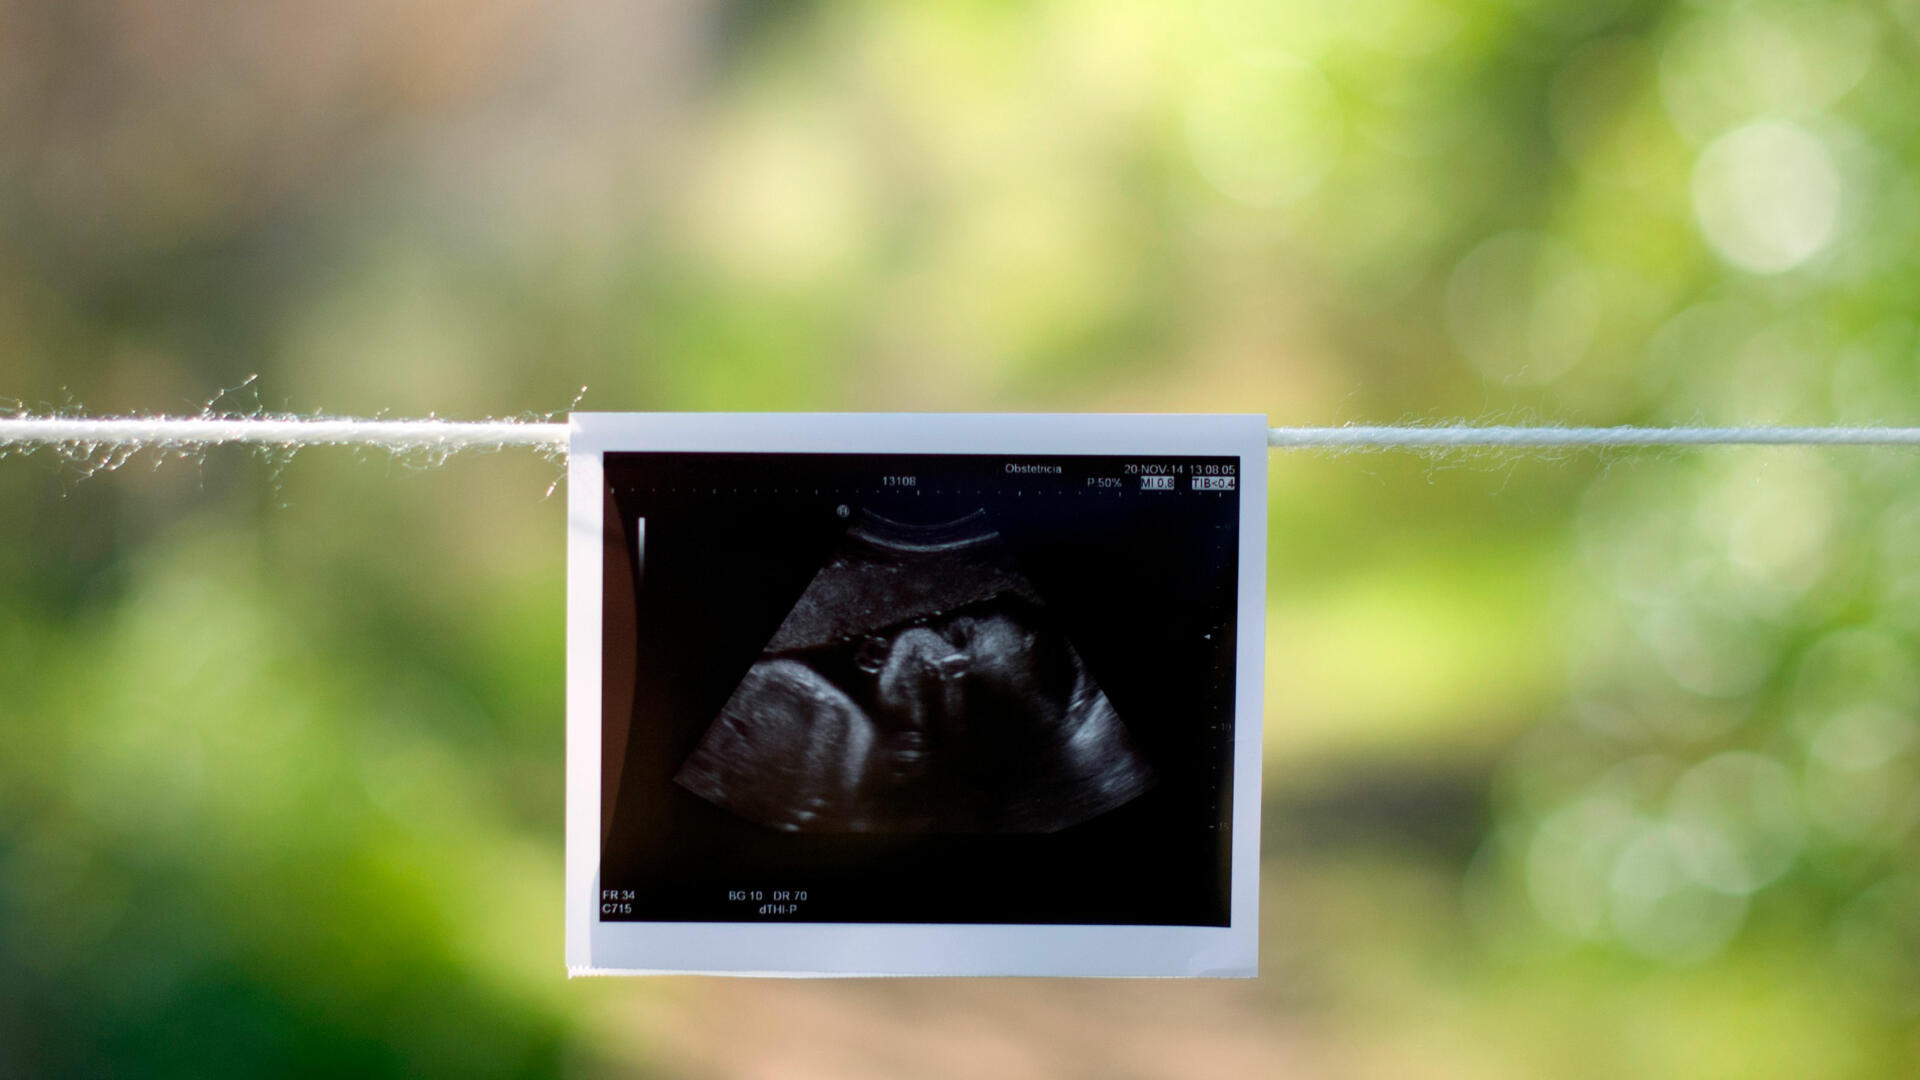

Dans les zones rurales, chaque grossesse non suivie est un risque de trop. Pour y remédier, le ministère de la Santé vient de recevoir des échographes mobiles, un renforcement capacitaire concret et ciblé qui pourrait changer la donne pour des milliers de femmes et de nouveau-nés.

Déployés au sein des structures sanitaires rurales, ils permettront d'assurer un meilleur suivi des grossesses, d'améliorer le dépistage des cancers du sein et de renforcer la prise en charge gynéco-obstétricale dans des zones jusqu'ici sous-équipées et insuffisamment couvertes.

La mortalité maternelle et néonatale demeure l'un des défis les plus pressants du système de santé togolais, particulièrement dans les communautés éloignées des plateaux techniques des grands centres urbains. L'accès à des outils de diagnostic performants au plus près des populations constitue une réponse directe et efficace à cette réalité.